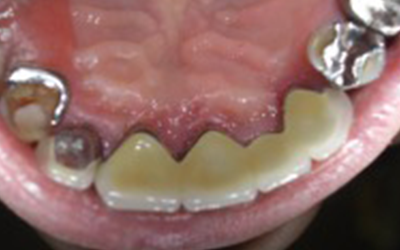

Aさん(70代・男性) インプラント

BEFORE

AFTER

Kさん(60代・女性) インプラント

治療内容

「入れ歯との組み合わせ」

現在入れ歯の人も、少ない本数のインプラントで対応が可能。

通常は全部インプラントがベストですが、入れ歯との組み合わせも可能です。

「入れ歯が安定する」「ガタガタしない」というメリットがあります。